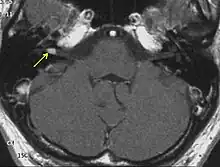

Neurofibromatosis type II (also known as MISME syndrome – multiple inherited schwannomas, meningiomas, and ependymomas) is a genetic condition that may be inherited or may arise spontaneously. The main manifestation of the condition is the development of bilateral benign brain tumors in the nerve sheath of the cranial nerve VIII, which is the "auditory-vestibular nerve" that transmits sensory information from the inner ear to the brain. Besides, other benign brain and spinal tumors occur. Symptoms depend on the presence, localisation and growth of the tumor(s). Many people with this condition also experience vision problems. Neurofibromatosis type II (NF2 or NF II) is caused by mutations of the "Merlin" gene,[2] which seems to influence the form and movement of cells. The principal treatments consist of neurosurgical removal of the tumors and surgical treatment of the eye lesions. Historically the underlying disorder has not had any therapy due to the cell function caused by the genetic mutation.

Pathology

The so-called acoustic neuroma of NF2 is in fact a schwannoma of the nervus vestibularis, or vestibular schwannoma. The misnomer of acoustic neuroma is still often used. The vestibular schwannomas grow slowly at the inner entrance of the internal auditory meatus (meatus acousticus internus). They derive from the nerve sheaths of the upper part of the nervus vestibularis in the region between the central and peripheral myelin (Obersteiner-Redlich-Zone) within the area of the porus acousticus, 1 cm from the brainstem.